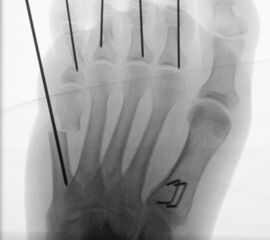

In der minimalinvasiven Fußchirurgie ist es unabdingbar, die Fräse in ihrer Position zum Knochen radiologisch zu kontrollieren, damit vulnerable Wachstumsfugen oder angrenzende Gelenke nicht verletzt werden. Zu diesem Zweck werden mit einem Bildwandler während der Operation die genaue Position der Fräse und der Osteotomieverlauf überprüft, was die Strahlenbelastung im Vergleich zu offenen Verfahren erhöht. Diese Strahlenbelastung hat potenziell einen schädigenden Einfluss auf den noch blutbildenden Knochen von Heranwachsenden. Gesicherte Landmarken am Fuß können die notwendige Zahl der Röntgenbilder und damit die Strahlung minimieren. Ist es erforderlich, mehrere Knochen zu osteotomieren, wie zum Beispiel im Bereich der Kleinzehen, werden anhand der Landmarken kleine Injektionsnadeln auf Höhe der geplanten Osteotomien vorgelegt und radiologisch im Bildwandler (BV) dokumentiert (Abb. 11). Ein solches Bild schafft eine gute Orientierung, sodass auf radiologische Kontrollen intraoperativ weitestgehend verzichtet werden kann.

Abb. 11: Lokalisation mehrerer Stichinzisionen mit einem Röntgenbild.

Zum Lesen der Bildbeschreibung und zur Vollansicht bitte das Bild anklicken. Bild: A. Helmers.